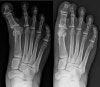

X-ray : 무지내반증(Hallux varus)